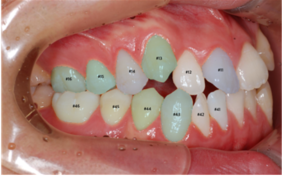

○ 객체 종류

- segmentation: 치아 경계, 충치, 입술 경계

- polyline: 치축, 안모정중선

- class: 교합면 관계

○ 객체 카테고리

| 카테고리 종류 | category_id 범위 | 설명 |

|---|---|---|

| 치아경계 | 0, 1, 2, 3, 4, 5, 8, 9, 10, 11, 12, 13, 16, 17, 18, 19, 20, 21, 24, 25, 26, 27, 28 29, | tooth number system FDI 에 매핑함 |

| categoty_id : FDI | ||

| 0~5:11~16, 8~13:21~26, 16~21:31~36, 24~29:41~46 | ||

| 충치 | 32 | |

| 입술경계 | 33 | |

| 치축 | 34 | |

| 안모정중선 | 35 | |

| 대구치관계 | 98,99,100 | 교합면 관계를 매핑함 |